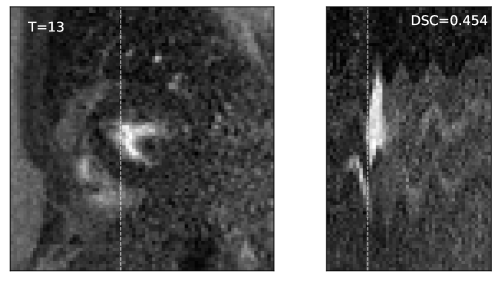

6. 6.

Evaluation metrics. The performance of combined computing was evaluated in terms of both registration and segmentation. The registration accuracy was calculated as the DSC on the propagated segmentation masks {𝒀jϕ^j}j=1Nsuperscriptsubscriptsubscript𝒀𝑗subscript^italic-ϕ𝑗𝑗1𝑁\{\bm{Y}_{j}\circ\widehat{\phi}_{j}\}_{j=1}^{N} with the registered images. The DSC was averaged over all pairs of the warped segmentation masks to produce the value. On the other hand, the segmentation accuracy was evaluated by the DSCs between the estimated posterior segmentation 𝒁^[2]superscript^𝒁delimited-[]2\widehat{\bm{Z}}^{[2]} and each warped segmentation mask 𝒀jϕ^jsubscript𝒀𝑗subscript^italic-ϕ𝑗\bm{Y}_{j}\circ\widehat{\phi}_{j}, where z^𝒙,k[2]=1superscriptsubscript^𝑧𝒙superscript𝑘delimited-[]21\widehat{z}_{\bm{x},k^{*}}^{[2]}=1 if and only if

k=argmaxk=1,,K{πk[2]j𝒥ρ^jk(ϕ^j(𝒙))j=1Nf^jk[t](μ𝒙,jϕ^j)}.superscript𝑘subscriptargmax𝑘1𝐾superscriptsubscript𝜋𝑘delimited-[]2subscriptproduct𝑗𝒥subscript^𝜌𝑗𝑘subscript^italic-ϕ𝑗𝒙superscriptsubscriptproduct𝑗1𝑁superscriptsubscript^𝑓𝑗𝑘delimited-[]𝑡superscriptsubscript𝜇𝒙𝑗subscript^italic-ϕ𝑗k^{*}=\operatorname*{arg\,max}_{k=1,\dots,K}\left\{\pi_{k}^{[2]}\prod_{j\in\mathcal{J}}\widehat{\rho}_{jk}(\widehat{\phi}_{j}(\bm{x}))\prod_{j=1}^{N}\widehat{f}_{jk}^{[t]}(\mu_{\bm{x},j}^{\widehat{\phi}_{j}})\right\}. (53)

Therefore, it was intended to measure errors in both registration and segmentation predictions.